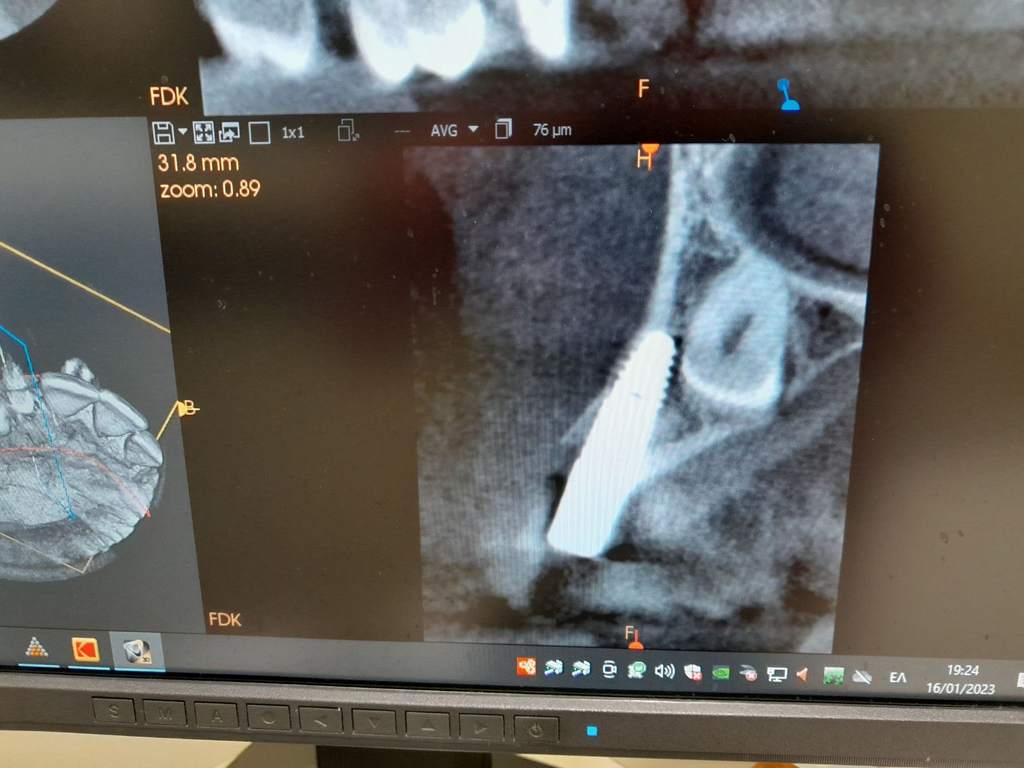

Σήμερα, στο «οπλοστάσιό» μας, έχει προστεθεί και η υπολογιστική τομογραφία κωνικής δέσμης (CBCT), οι εικόνες της οποίας είναι ιδανικές τόσο για να μας πληροφορήσουν για τη μορφολογία του συστήματος των ριζικών σωλήνων αλλά κυρίως να μας βοηθήσουν στη διάγνωση των βλαβών στο άκρο της ρίζας, στην έκταση αυτών των βλαβών και τη σχέση τους με παρακείμενες ανατομικές δομές (π.χ. ιγμόρειο).

Στις ελάχιστες περιπτώσεις που ένα δόντι δεν μπορεί να σωθεί, δεν θα διστάσουμε να το αντικαταστήσουμε με ένα εμφύτευμα. Η εμφυτευματολογία αποτελεί μια έγκυρη θεραπευτική επιλογή αντικατάστασης δοντιών που δεν σώζονται, με όσο το δυνατό πιο αισθητικό και συντηρητικό τρόπο. Η χειρουργική τοποθέτηση των εμφυτευμάτων πραγματοποιείται από τον εμφυτευματολόγο κ. Μπαρμπετσέα Ανδρέα, ενώ στη συνέχεια η προσθετική αποκατάσταση επί των εμφυτευμάτων , πραγματοποιείται στο ιατρείο μας.